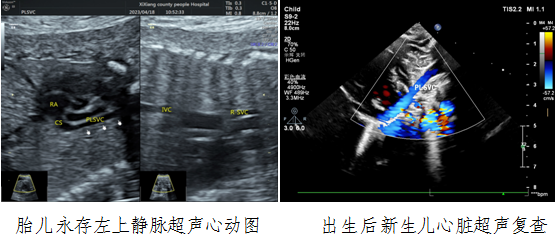

病例一,30岁,孕22w+,G2P1,既往产检未见胎儿心脏结构异常。2023年4月到西乡县医院例行常规产前超声检查,五楼自拍

对口帮扶贾玄慧医生,超声发现胎儿存在先天大血管发育异常——永存左上腔静脉,指导孕妇进行产前咨询及产后随访。胎儿出生后1天,贾玄慧医生立即对该新生儿进行了心脏复查,结果确诊永存左上腔静脉诊断明确。